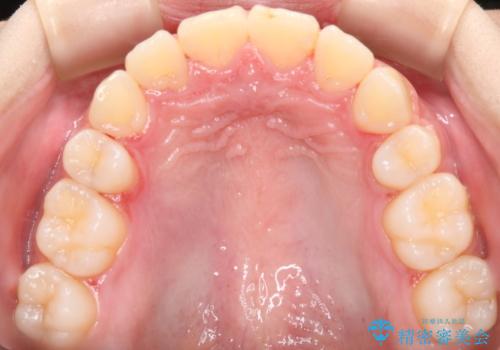

- 出っ歯が気になるとご相談にいらした方です。抜歯して歯を並べました。深かった噛み合わせも改善させることが出来ました。

噛み合わせが元々深い方は一般的に噛む力が強く、治療に時間がかかる傾向にあります。治療前の想定よりも短期間でスムーズに治療を終える事ができ、大変喜んでいただけました。リテーナーによる保定もしっかり行っていただいており、後戻りなく快適にすごして頂けているとのことです。